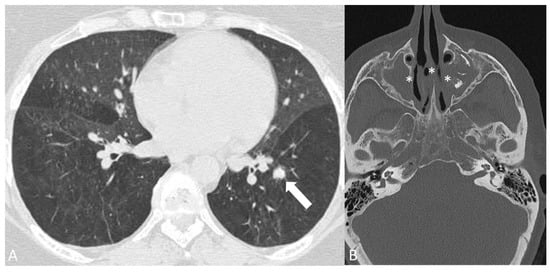

2.3.1. Granulomatosis with Polyangiitis

2.3.2. Eosinophilic Granulomatosis with Polyangiitis